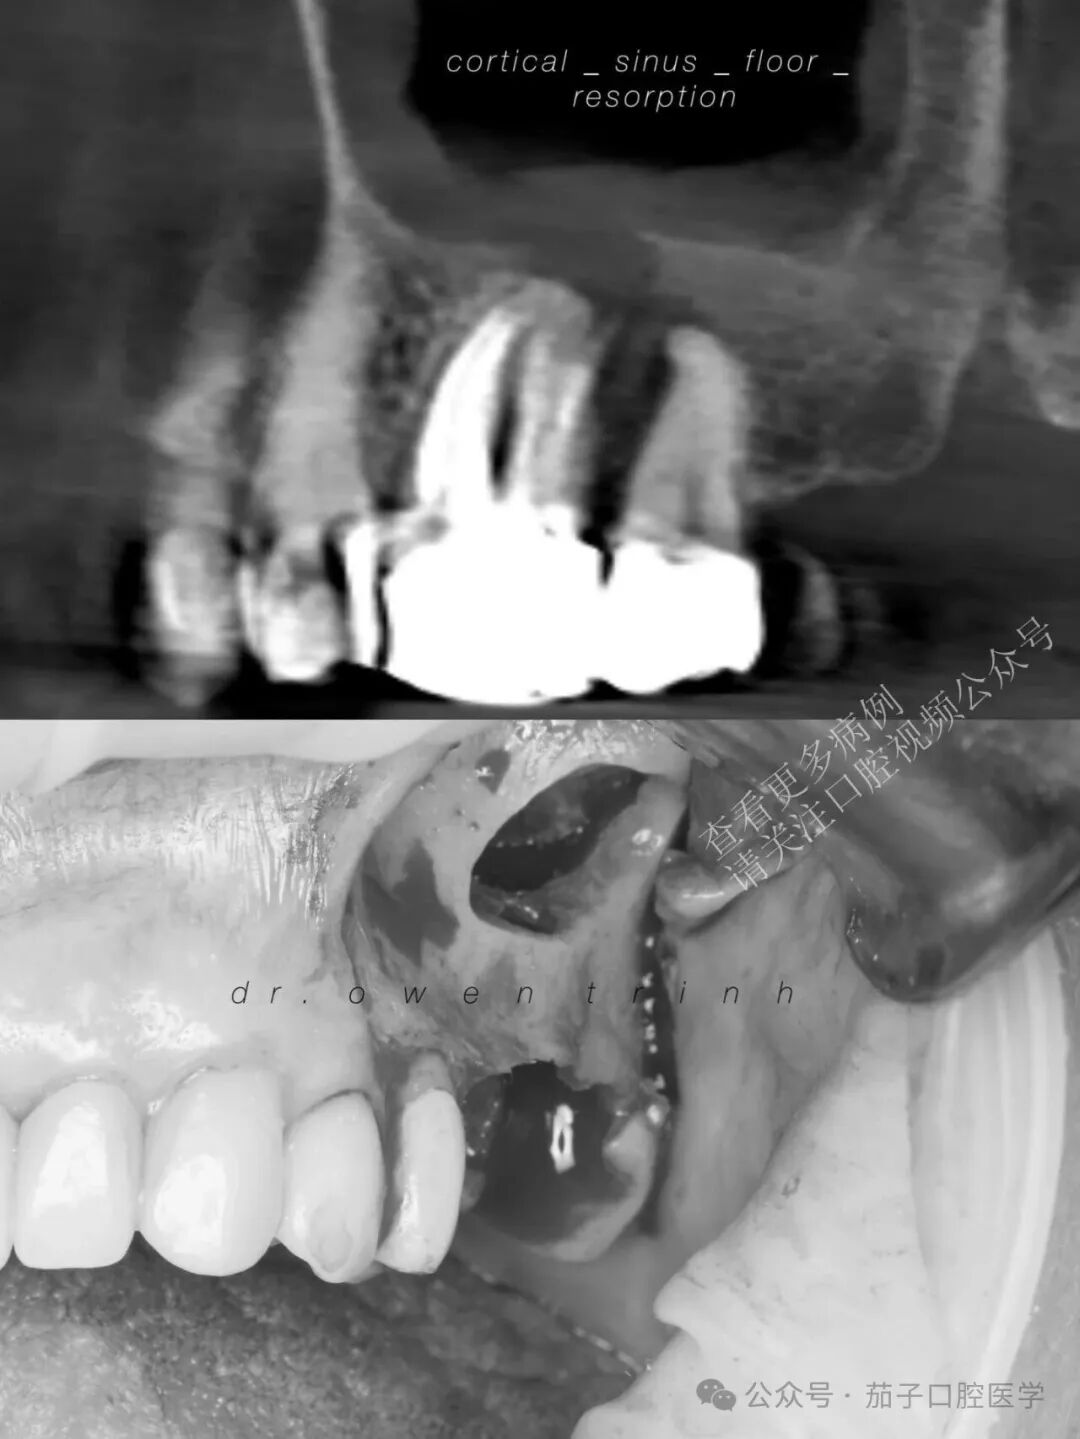

CBCT显示慢性根尖脓肿,已破坏上颌窦皮质底壁及#14与#15牙间的全部邻间壁。患者同意接受拔牙联合外侧上颌窦提升术,为后续种植体植入做准备。

由于增厚的上颌窦黏膜(慢性上颌窦炎)与脓肿之间存在强烈的粘连/附着,上颌窦黏膜很难与根尖牙槽骨壁分离(在抬升黏膜时阻力极大),这与气化良好的上颌窦底黏膜截然不同。此外,由于缺乏气化的牙槽突骨质,使得抬升上颌窦黏膜变得困难,因为医生必须使用上颌窦刮匙在14号牙和15号牙根尖牙槽骨的每一个转角和曲度中进行操作。